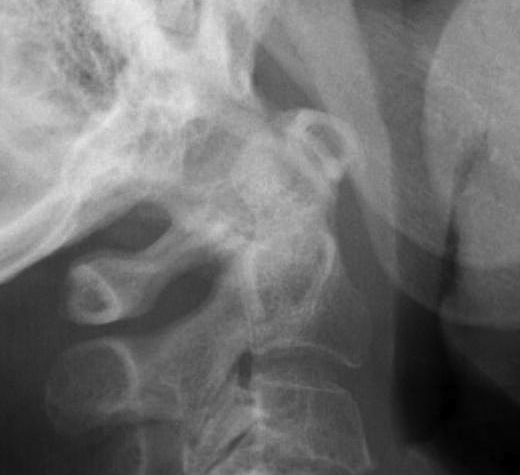

Subaxial Subluxation (SAS)

Definition

Anterior subluxation of one vertebral body on another

Results in spinal stenosis

Diagnosis

A. Instability on Flexion / Extension views

- > 3mm

- > 11o

Anterior subluxation of C3 on C4

B. Space available for cord / SAC

- subaxial canal diameter on lateral

- < 13 mm high incidence neurology

Pathology

Facet erosions / ligament incompetence

May see at multiple levels with stepladder type deformity & kyphosis

Can occur beneath previous cervical fusions including C1/C2